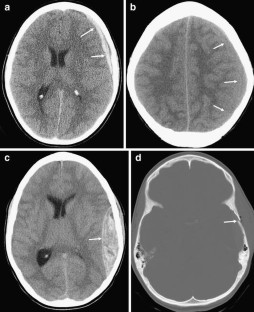

Fig. 1